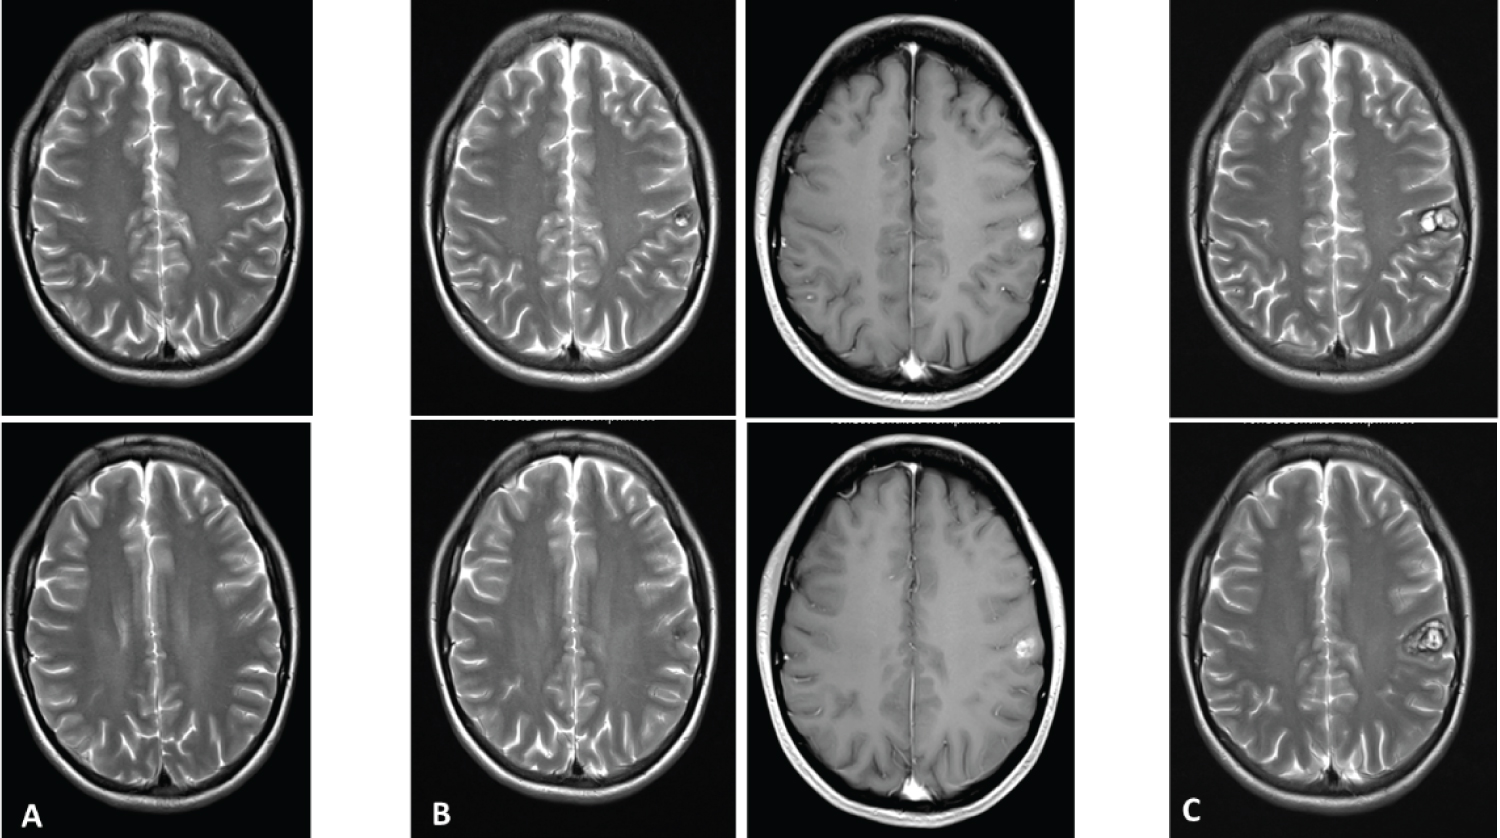

In December 2017, apart from showing the circumscript postischemic lesion in the left cerebral hemisphere, an MRI of the head did not reveal any significant abnormalities (Figure 1A). On January 22, 2020, a small, contrast-enhancing hemorrhagic lesion could be seen in the left postcentral gyrus, more precisely in the soma-tosensoric area representing the right arm (Figure 1B and Figure 2). In April 2020, the lesion had tripled in volume (Figure 1C).

Figure 1: (A) T2-weighted MRI taken in Dec 2017, showing no lesion in the somatosensory cortex; (B) T2- and post-contrast T1-weighted images taken in Jan 2017. De novo cavernoma in the left somatosensory cor-tex; (C) Follow-up T2-weighted MRI three months later, the lesion had tripled in volume and the patient suf-fered from left-sided cervicobrachialgia and dysesthesia. View Figure 1